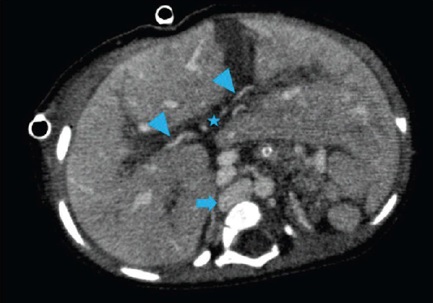

In the postoperative period, due to the persistence of cyanosis, further investigation and imaging study were indicated, which:

Showed difuse dilatation of right heart chambers on qualitative analysis of pulmonary trunk and arteries (Figure 1B), aortic sinus, and ascending thoracic aorta in relation to body surface area. Apparent dilatation of right pulmonary veins and its ostia.

Showed medialized liver and absence of inferior vena cava (IVC) intrahepatic segment. Infrahepatic portion continuing with the azygos system at the thoracic cavity level (Figure 3). Also, ectasia of the splenomesenteric venous circulation, and hepatic and superior mesenteric arteries, polysplenia, and intestinal malrotation (Figures 4 and 5).

Not identifed the portal vein inferring agenesis, with mesenteric-caval communication at renal venous drainage level, as shown in Figure 3. There were signs suggestive of hepatic peribiliary fibrosis (at the expense of focal intrahepatic bile duct ectasia) and moderate ascites, typical findings related to Abernethy type I malformation.